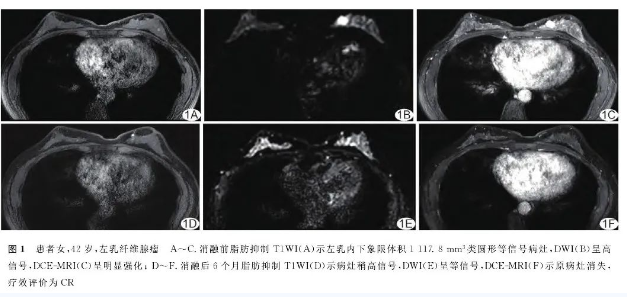

消融前,63例66个病灶脂肪抑制T1WI均呈低或等信号,DWI呈均匀或不均匀稍高信号,DCE-MRI表现为均匀或不均匀明显强化;消融后即刻T1WI见消融区域呈低-中混杂信号,ADC图未见明显改变,完全消融时DCE-MRI呈不强化或环状强化;消融后6个月,原病灶脂肪抑制T1WI呈不均匀稍高信号,DWI信号较消融前稍降低或仍为均匀、不均匀稍高信号,DCE-MRI呈环状强化或不强化。见图1。